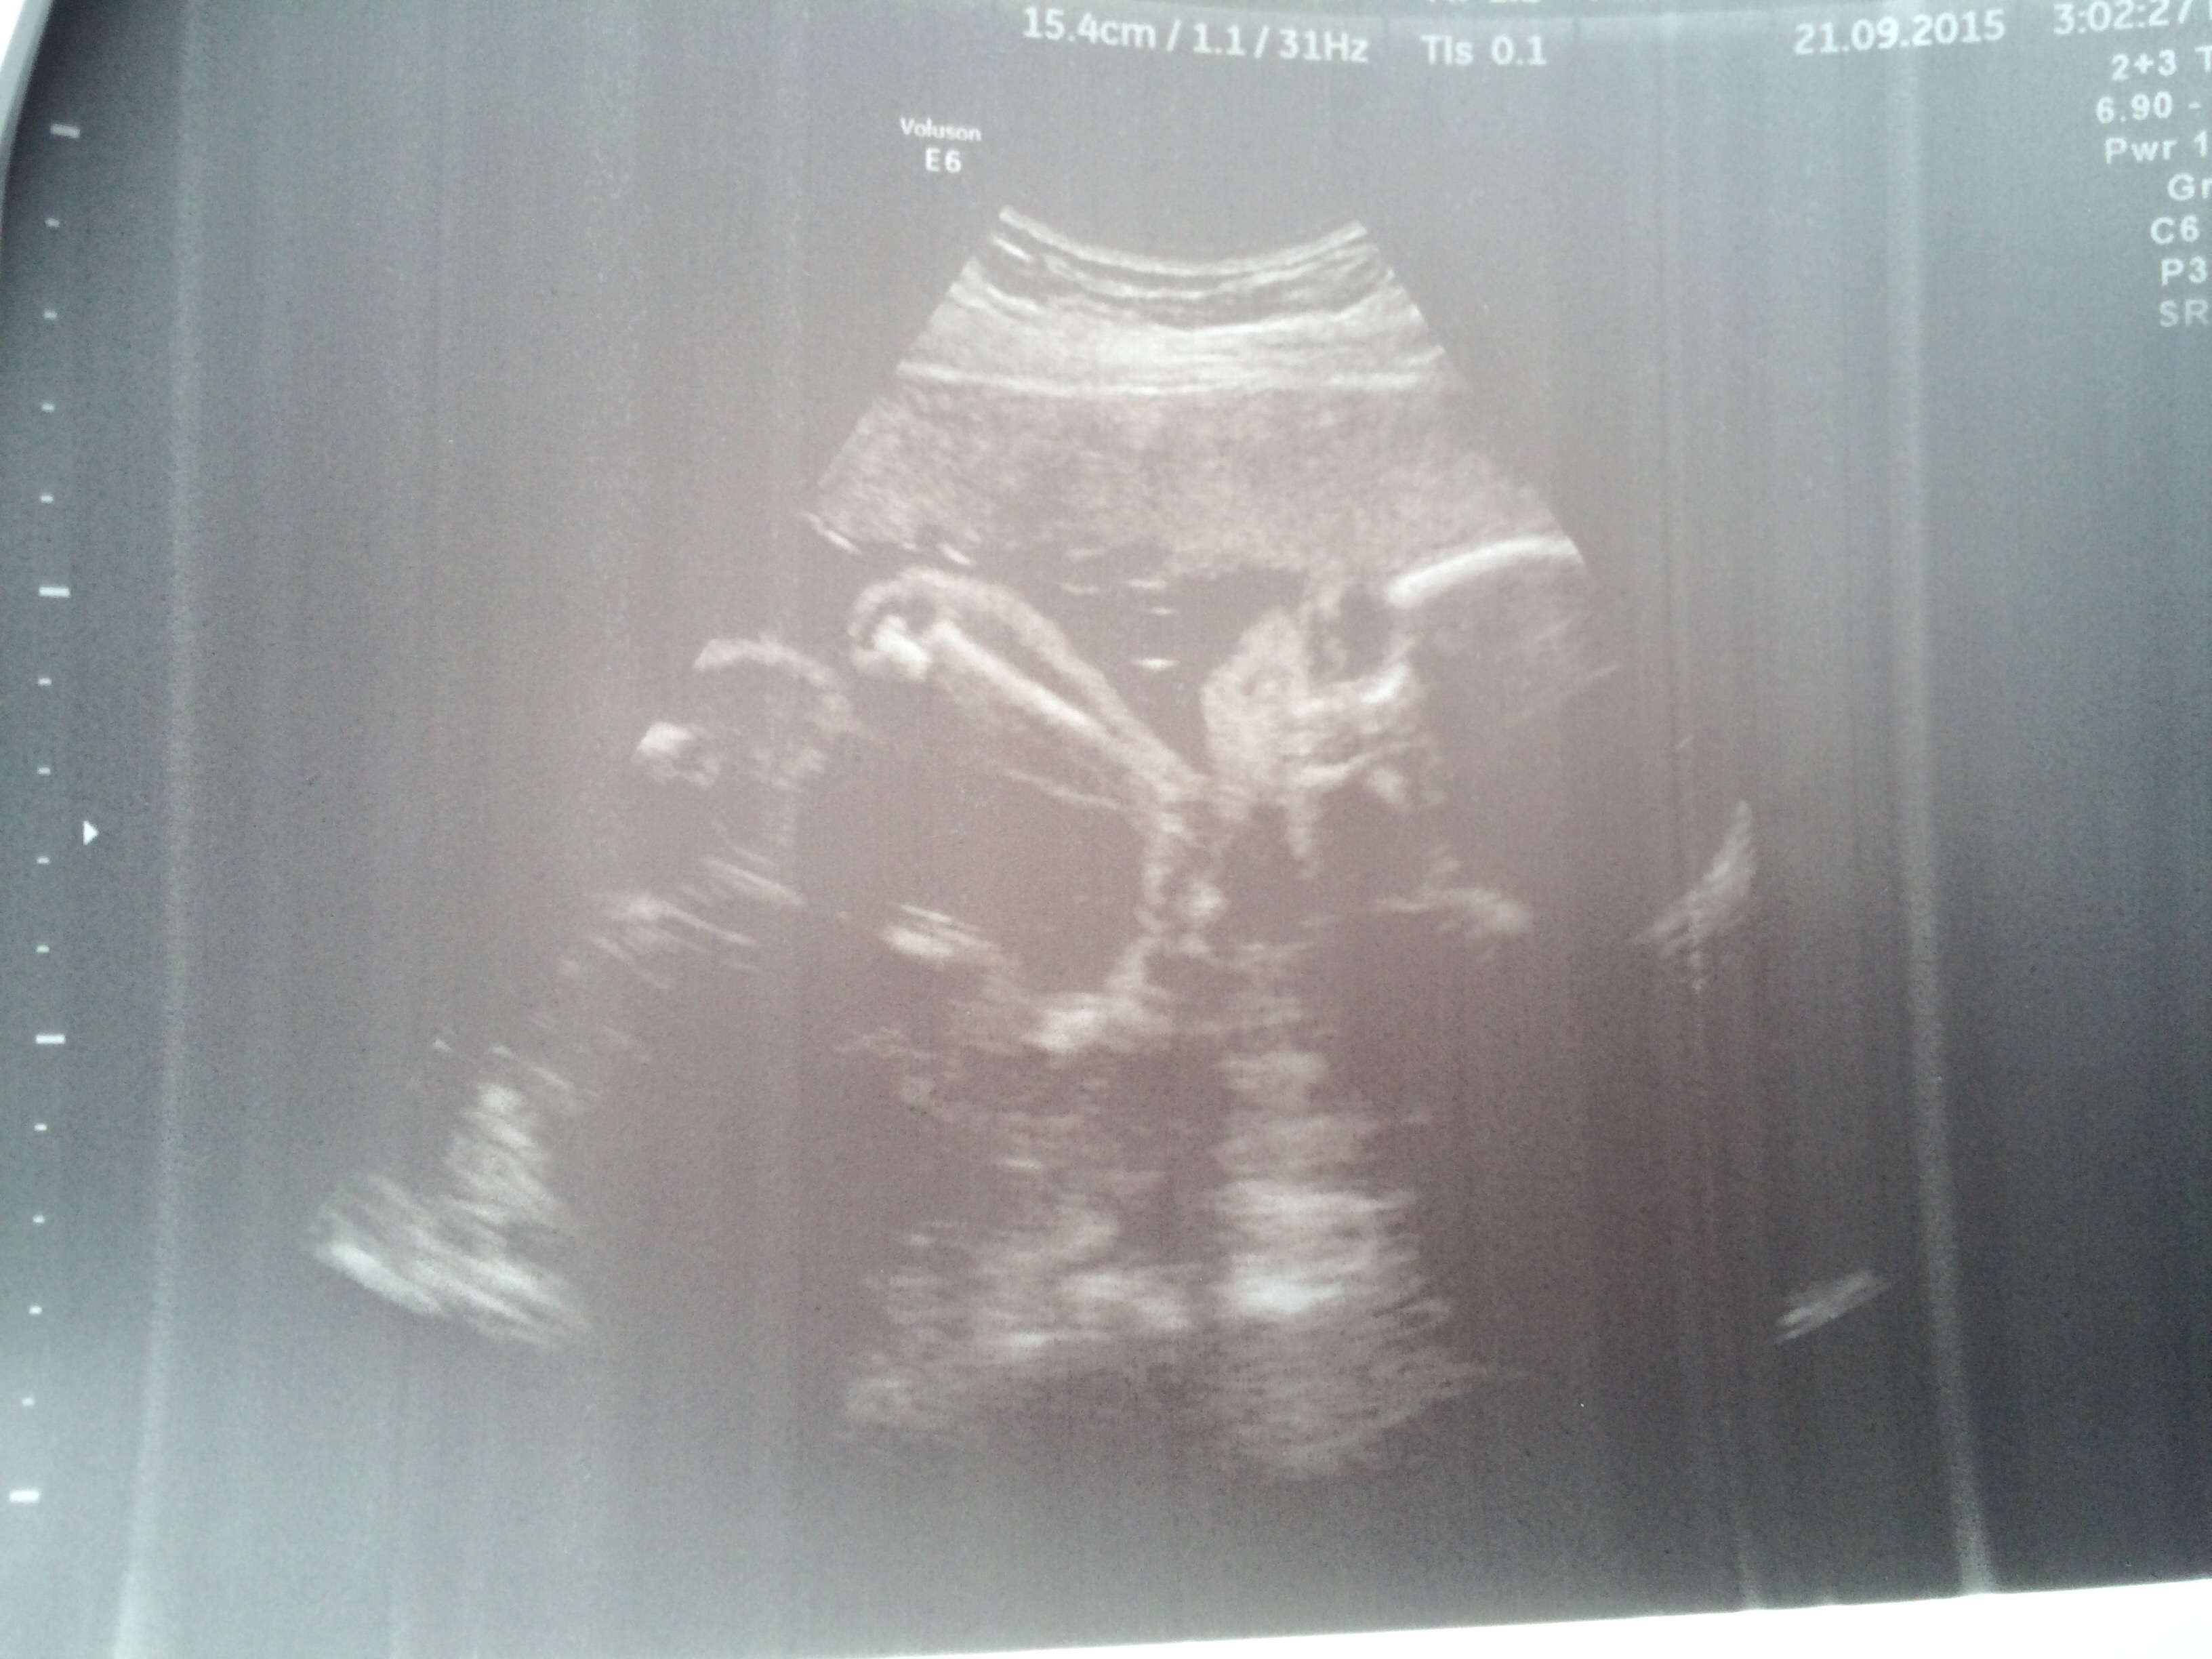

Froschi macht sich jetzt mit ihren 32cm und 760g immer mehr bemerkbar. Sie liegt jetzt auch schon mit dem

Kopf nach unten, mal sehen ob das so bleibt oder sie sich nochmal dreht. Trisi ist ja immer mit dem Kopf unten geblieben.